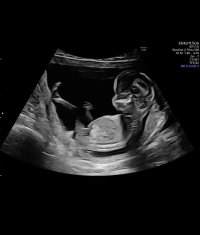

Åå, så kjedelig med dårlige bilder :/.. Jeg har dette også, men her ser man heller ikke stort. Jordmor sa ingenting om hva hun trodde eller noe som helst om kjønnet..Disse bildene var veldig dårlig til å være 14 uker. har du flere fra denne eller tidligere? burde være lett å se kjønn når man er så langt på vei. det på bilde nr 1 er ikke nub, det er en del av benet som har kommet med på bildet. Jeg tror det er jente da det ville vært veldig synlig i uke 14 om det var gutt. Ser og lang hvit strek på flere av bildene som samsvarer med jentenub.

? Er 13+1 her